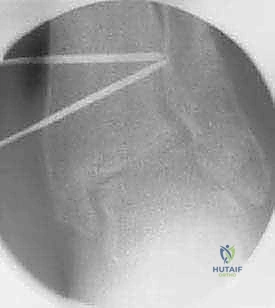

باستخدام أدوات قطع عظمية دقيقة جداً (مناشير جراحية متأرجحة)، وتحت توجيه جهاز الأشعة السينية المباشر في غرفة العمليات (C-arm)، يتم إحداث القطع في عظم الظنبوب في المكان المخطط له مسبقاً، مع الحفاظ على جزء بسيط من القشرة العظمية في الجهة المقابلة لتعمل كمفصلة (Hinge).

يتم فتح القطع العظمي بلطف وتدريجياً للوصول إلى الزاوية المصححة التي تم حسابها. هذه الخطوة هي جوهر العملية، حيث يتم استعادة المحور الميكانيكي السليم للساق.